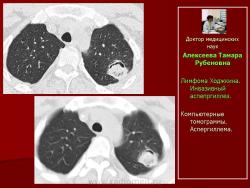

Рис.18. Б-ной Г. Лимфома Ходжкина. Инвазивный аспепргиллез.

Компьютерные томограммы. Аспергиллема.

Рис. 19. А. Б-ной К. НХЛ. и Б. Б-ной В. НХЛ. Инвазивный аспепргиллез.

Компьютерные томограммы. Аспергиллемы. Симптом «ореола».

Рис. 20.Б-ной Т. Лимфома Ходжкина

Компьютерные томограммы Множественные полостные образования с массой мицелия внутри.

Следует отметить, что во всех наблюдениях полостные образования – аспергиллемы появлялись в неизмененной ранее легочной ткани.

Независимо от формы поражения нами отмечено, что при инвазивном аспергиллезе информативным признаком являлось наличие полостных образований.